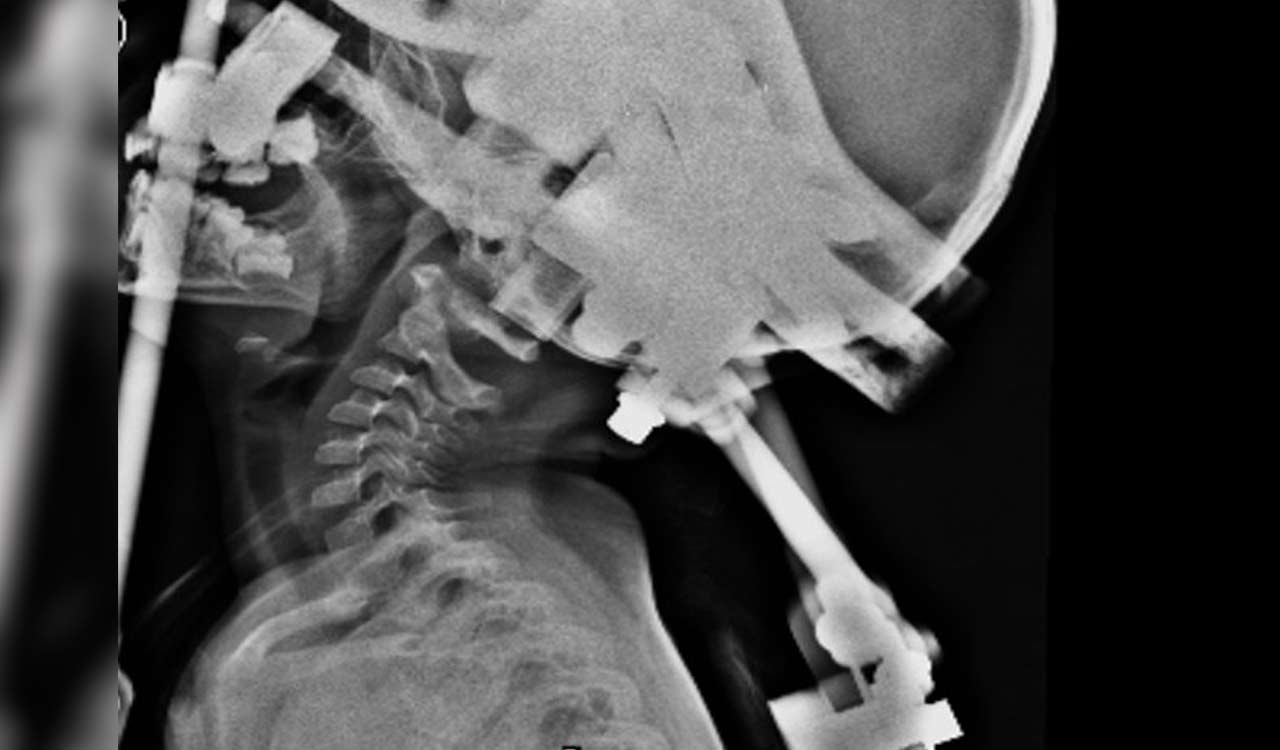

Hyderabad: Doctors at Krishna Institute of Medical Sciences (KIMS), Kondapur saved the life of a three-year-old girl suffering from Atlanto-axial instability, a condition in which the infant’s neck bones were damaged, making it difficult for her to hold the neck properly.

Also Read